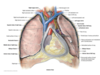

What is the coelimic cavity? What happens to it during development?

Coelimic cavity is a fluid filled body cavity which gives rise to the pleural cavity, pericardial cavity, peritoneal cavity